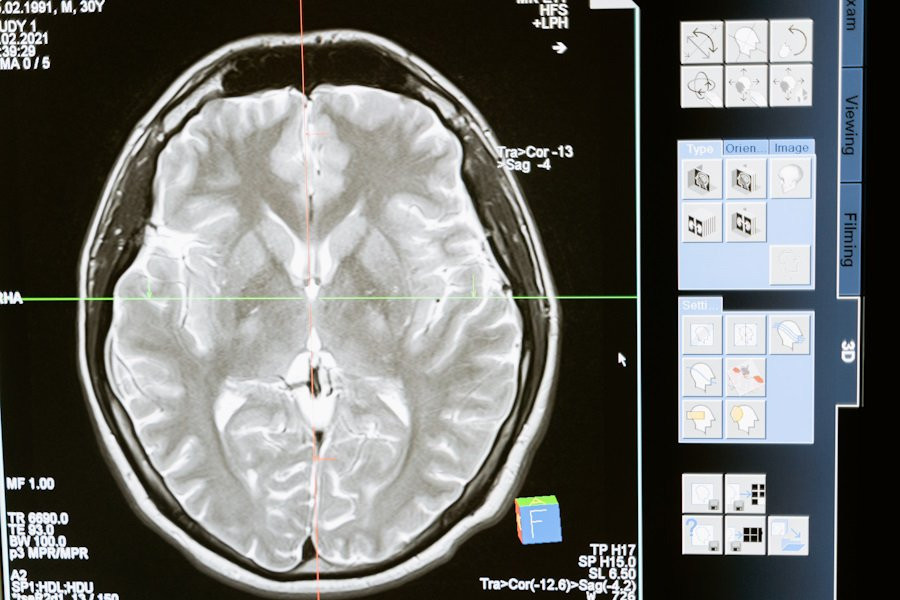

Учёные сфокусировались на разных группах нейронов в гиппокампе — области мозга, отвечающей за формирование воспоминаний. Они обнаружили, что когда мозг кодирует новое воспоминание, оно одновременно записывается в нескольких «следах» в этих нейронных группах. Две из таких копий создаются в разных субпопуляциях нейронов: одни из них рождаются на раннем этапе, а другие — позже. Эти нейронные группы активируются и развиваются по-разному после того, как воспоминание было записано.